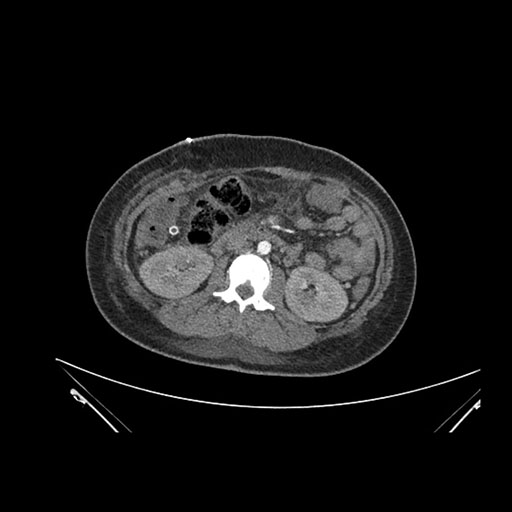

Axial Arterial

Imaging analysis

Based on initial findings, which issue(s) would you be most concerned about?